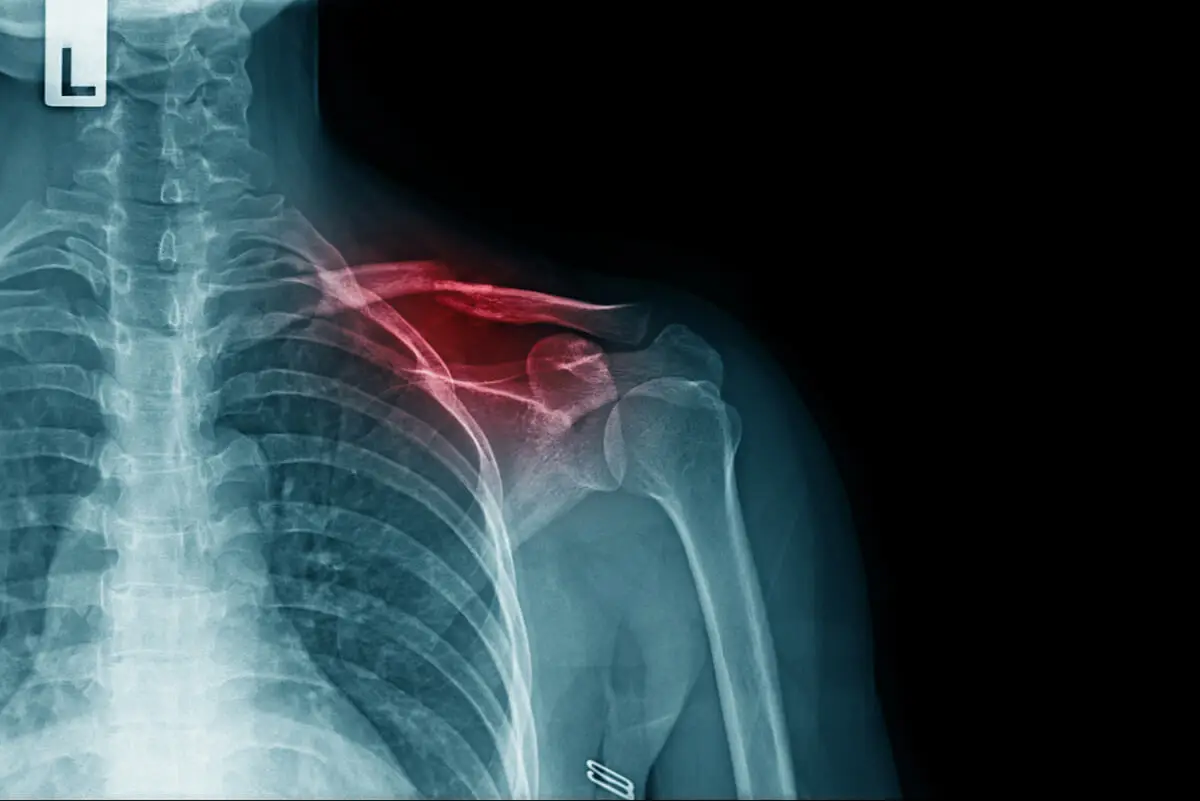

Una fractura de clavícula, como la que padece Mikel Landa por su caída en el Giro de Italia 2021, es una solución de continuidad en el hueso de la parte superior del tórax. Es decir, se trata de una interrupción en el recorrido natural que tiene el tejido óseo en esta zona.

La clavícula es una estructura anatómica que conecta el esternón con la escápula. De manera tradicional, se la divide en 3 segmentos para su estudio, considerando que las roturas pueden aparecer en la zona más cercana al cuello, en la más cercana al hombro o en la mitad.